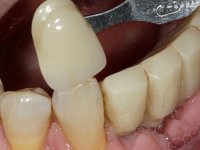

After an imaging study, the placement of two implants of 3.3 mm in diameter and 10 mm in length was planned. On the day of surgery, teeth 42 and 32 were extracted and the implant was removed. The implants were placed in the area of the alveoli, taking care to slightly lingualize their positioning. An impression was made using the open tray technique with the flap open for the fabrication of the immediate provisional bridge. While the impression was taken to the laboratory, tall healing screws were placed and the surgical wound was sutured. The patient waited 2 hours in the waiting room while the temporary bridge was made in the laboratory. An immediate screw-retained provisional bridge was placed and its seating was controlled by imaging. After 3 months, the final impression was made using an open tray technique. In this consultation, we took the opportunity to polish the temporary bridge with rubber cups so that the soft tissues could mature in better conditions. Information was collected to better characterize the monolithic structure in Zr. Color guides were used for the coronal and gingival ceramics. In the laboratory, a bridge was made in Zr. bolt-on that has been carefully characterized. After approval by the patient, it was definitively placed in the mouth. Tightening was performed with a dynamic wrench with a torque of 35 N. The holes were covered with Teflon and filled with composite resin.